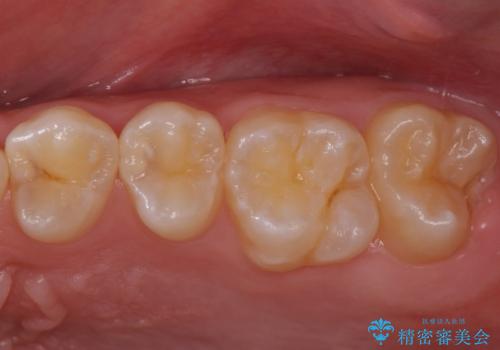

歯と歯の間の虫歯 セラミックインレーでの治療

- 検査の結果、歯と歯の間に大きな虫歯が確認されました。

セラミックでの治療をご希望されたため、セラミックインレーでの治療を行いました。

今回は残せる歯の厚みが十分確保できたため、インレーでの修復処置となりました。